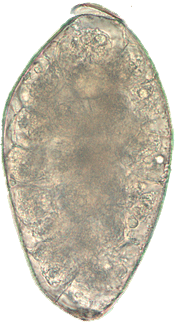

| Paragonimus westermani | 85 µm x 53 µm. Range, 68-118 µm x 39-67 µm. | Ovoidal or elongate with thick shell. Operculum is slightly flattened and fits into shoulder area of shell. Posterior end is thickened. Egg often asymmetrical with one side slightly flattened. | Yellow brown to dark brown. | Unembryonated. Filled with yolk material in which a germinal cell is imbedded. Cells are irregular in size. | Found in sputum, occasionally in feces. Resembles egg of D. latum but is larger, slightly asymmetrical and the operculum is smaller and flatter. The widest part of the Paragonimus egg is usually anterior to the center ; in a D. latum, the widest area is around the center. |

Figure 5: Trematode Eggs Found in Stool Specimens of Humans

Paragonimus westermani1 |

Paragonimus westermani1